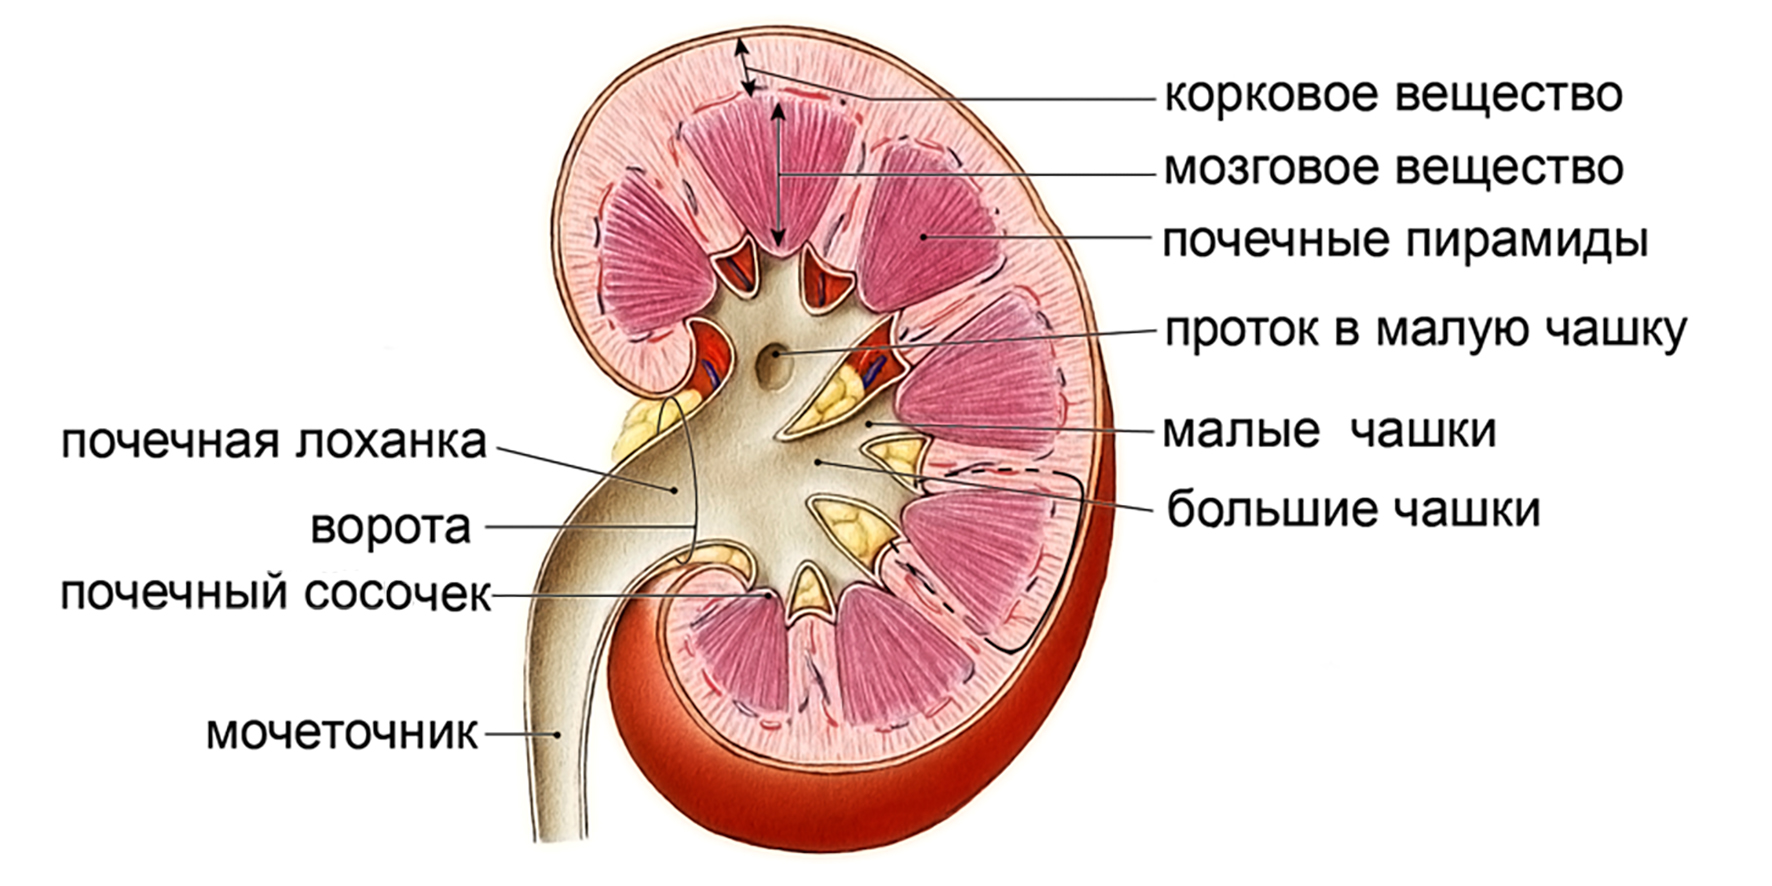

Интраренальная лоханка: рентгеновские снимки и примеры